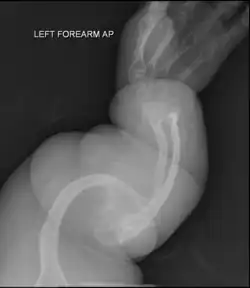

2-й тип может быть далее разбит на подклассы A, B, C, различаемые радиографическим анализом длинной трубчатой кости и рёбер.

Остеосинтез штифтом

При остеосинтезе штифтом изогнутая кость сначала многократно остеотомируется, чтобы затем бусообразно нанизывать костные сегменты на интрамедуллярный гвоздь. Сначала для этого использовались жёсткие штифты. В растущей кости, однако, такие штифты приходилось периодически заменять, так как кость однажды становилась длиннее штифта, вследствие чего штифт не был больше способен служить поддержкой для кости. Следовали фрактуры в этих незащищённых областях. Поэтому в 1963 году ортопедами был сконструирован выдвижной штифт. При росте кости два сегмента штифта выдвигаются друг из друга по принципу устройства подзорной трубы и как бы растут вместе с костью.